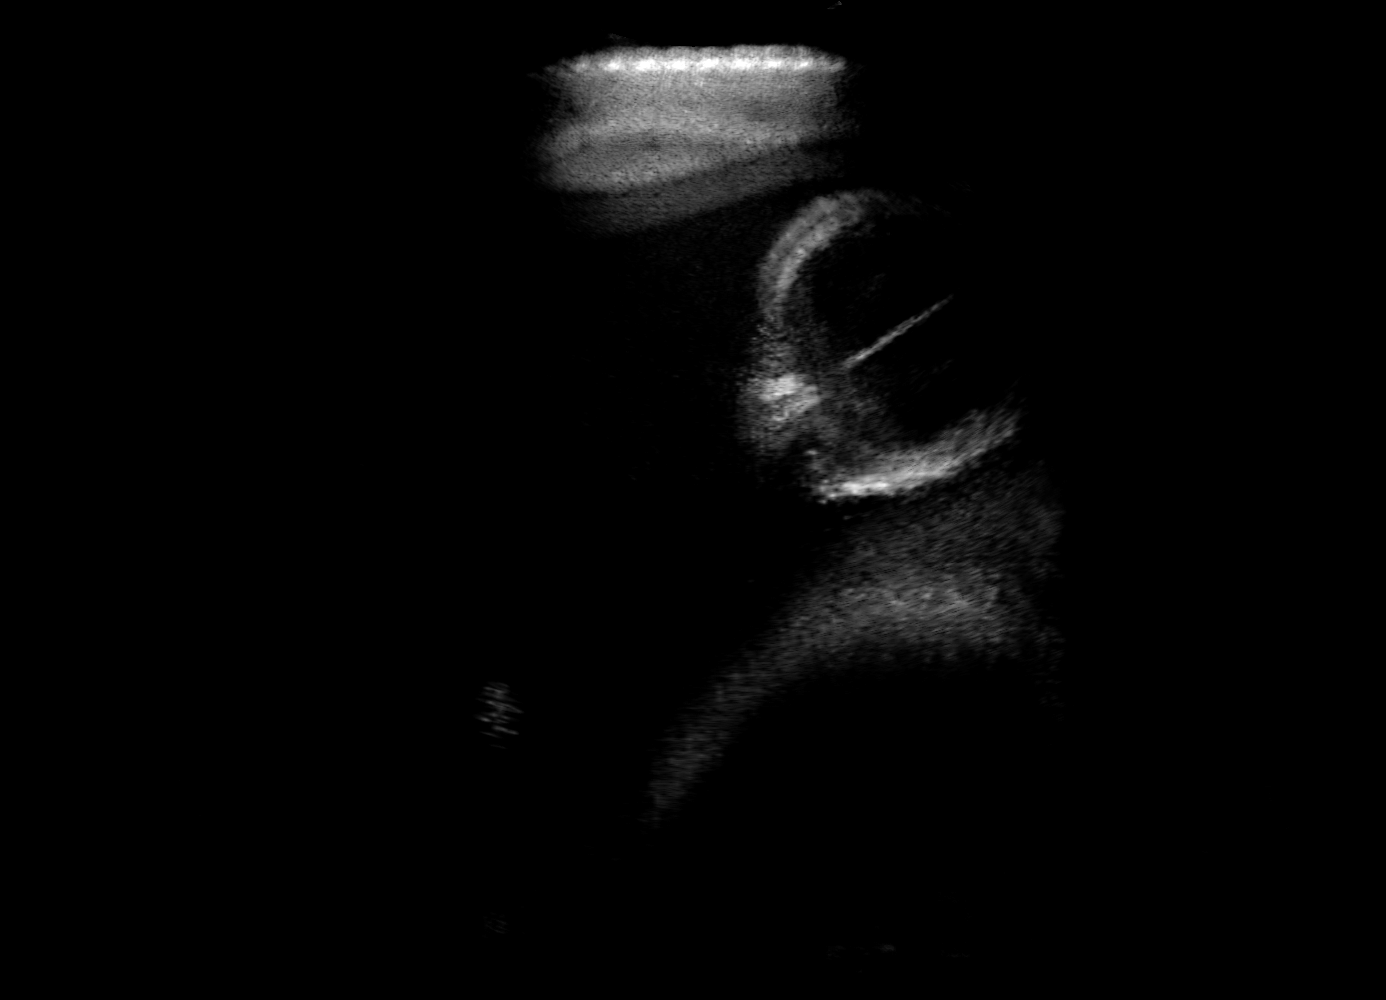

Qualitative evaluation.

Fig. 2 depicts the qualitative results for all the models mentioned above, with arrows pointing at structures relevant to discussion points below. The visual results of the ablated variants of SA2H show substantial quality degradation compared to the full SA2H model, demonstrating the importance of each proposed architectural contribution. Given only segmentation map in the network input, SA2H-att fails to generate acoustic shadows, e.g. those cast by the ribs. Detailed structures such as the cervical vertebrae are blurred out in the SA2H-concat results, which also contain hallucinated structures mainly due to insufficient preservation of input information along the encoding-decoding path. With SA2H-conv, checkerboard artefacts are observed due to the lack of proposed additional stride-1 convolutional layers. SA2H-noise without any explicit noise input is seen to be sub-optimal at generating textural details. The baseline method NSA2H fails to preserve anatomical structures and acoustic shadows in all cases, while the simulated textures also show significant artefacts such as checkerboard patterns. Realism of different simulation aspects may become relevant given different clinical applications and scenarios. For instance, improved structural preservation, e.g. with the hyperechoic bony structures such as the skull and the ribs, of the final model over its ablated variants and NSA2H may prove relevant in fetal head measurements, while the textural improvements facilitating screening fetal organ maturity, e.g. lungs. Compared to the silver-standard model LSA2H with a low-quality rendered image as additional input, SA2H is seen to be on par in structural preservation. Note that shadowing on homogenous regions (e.g. the rib shadowing on the homogenous lung region on the 4th column of Fig. 2) with our proposed method SA2H is represented more faithfully compared to LSA2H, whereas shadows on structurally complex regions (e.g. the skull shadowing around the heart and surrounding tissues on the 3rd column of Fig. 2) are suboptimal with our SA2H. Therefore, one may have to evaluate our method given particular simulation tasks, e.g. its clinical validity for fetal heart exams. However, even with low quality rendered images, LSA2H leads to artificial enhancements of intensities, lack of acoustic shadows, and low-quality textures especially near the probe, for which SA2H yields satisfactory results as illustrated in Fig. 2.

(a) Target

(b) SA2H

(c) SA2H-att

(d) SA2H-concat

(e) SA2H-conv

(f) SA2H-noise

(g) NSA2H

(h) LSA2H